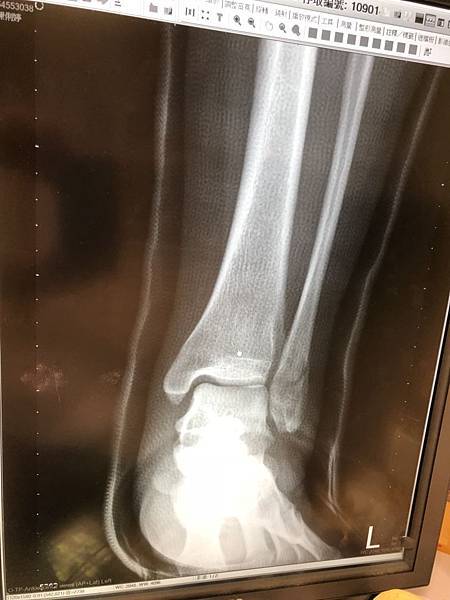

因此,吃兩個禮拜水藥的效果,連放三張讓大家比較,從上到下分別是受傷當天、沒吃藥兩周、吃藥兩周

第四周的照片,靠中心的裂痕明顯糊掉,看來進展不錯